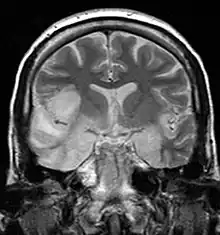

MRI scan image shows high signal in the temporal lobes and right inferior frontal gyrus in someone with herpes simplex encephalitis.